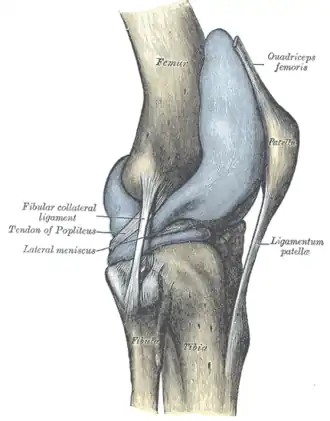

![]() Правый коленный сустав, сбоку. | |

Коле́нный сустав, коле́но (лат. articulatio genus) — сустав, соединяющий бедренную кость, большеберцовую кость и надколенник. Является сложным (в образовании сустава участвуют три кости), комплексным (содержит мениски). По форме является мыщелковым.

Анатомия

В передней части сустава расположен надколенник (коленная чашечка). Надколенник и четырёхглавая мышца бедра соединены сухожилием, продолжением которого является связка надколенника. В связочный аппарат входят:

- боковые (малоберцовая и большеберцовая коллатеральные)

- задние (подколенная, дугообразная, связка надколенника, медиальная и латеральная поддерживающие)

- внутрисуставные (крестообразные, поперечная связка колена (между менисками)

Крестообразные связки находятся в полости коленного сустава. К разрывам их приводят запредельные движения в коленном суставе.

- Передняя крестообразная связка (лат. lig. cruciatum anterius) начинается от задневерхней части внутренней поверхности наружного мыщелка (костного выступа) бедренной кости, пересекает полость коленного сустава и прикрепляется к передней части межмыщелкового возвышения большеберцовой кости также в полости сустава. Эта связка стабилизирует коленный сустав и не даёт голени чрезмерно смещаться вперёд, а также удерживает наружный мыщелок большеберцовой кости.

- Задняя крестообразная связка коленного сустава (лат. lig. cruciatum posterius) начинается от передневерхней части боковой поверхности внутреннего мыщелка бедра, пересекает коленный сустав и прикрепляется к наружной части межмыщелкового возвышения большеберцовой кости. Она стабилизирует коленный сустав, и удерживает голень от смещения назад.

Суставные поверхности костей покрыты хрящом. Между сочленяющимися поверхностями бедренной и большеберцовой костей имеются внутренний и наружный мениски, представляющие собой серповидные (формы полулуний) хрящи. Коленный сустав имеет несколько синовиальных сумок:

Передний и латеральный вид колена.